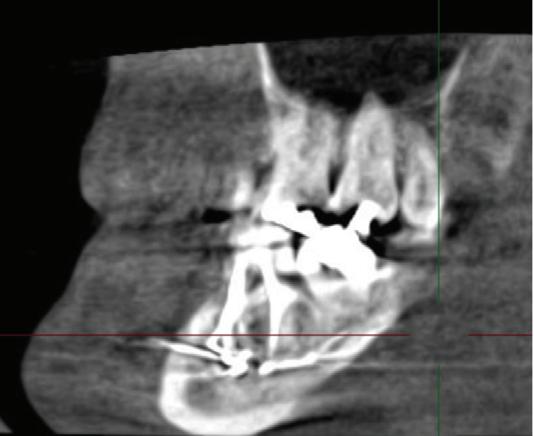

A unilateral sagittal split osteotomy was performed using piezosurgery to protect the nerve. The alveolar nerve, extending from the apical region of the left first and second molars to the mental foramen, was uncovered, and a meticulous dissection was performed to release it from the canal. Notably, rigid paste debris was observed in proximity to and within the nerve canal. The nerve exhibited signs of swelling and was surrounded by granulation tissue (Figures 4 and 5 ).

A thorough cleaning procedure ensued, followed by the repositioning of the two mandibular cortices, securing them in place with AO 5mm diameter

FIGURE 4: Unilateral sagittal split osteotomy.

FIGURE 5: The root canal filling material being removed from the canal.

FIGURE 6: Postoperative orthopantomogram showing almost complete retrieval of the material from the canal.

bicortical screws, and without insertion of intermaxillary fixation (IMF) screws. Orthodontic brackets were used to stabilise the occlusion for six weeks ( Figure 6 ).